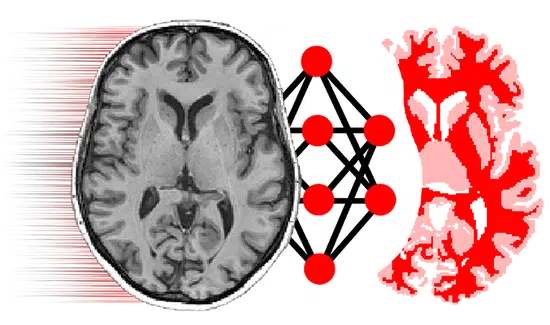

We design learning-based approaches for multi-modal reasoning

Medical imaging is a core source of information in our research

Open source PyTorch implementation of “Dorent, R., Booth, T., Li, W., Sudre, C. H., Kafiabadi, S., Cardoso, J., … & Vercauteren, T. (2020). Learning joint segmentation of tissues and brain lesions from task-specific hetero-modal domain-shifted datasets. Medical Image Analysis, 67, 101862 (📖).”

NiftyMIC is a Python-based open-source toolkit for research developed within the GIFT-Surg project to reconstruct an isotropic, high-resolution volume from multiple, possibly motion-corrupted, stacks of low-resolution 2D slices. Read “Ebner, M., Wang, G., Li, W., Aertsen, M., Patel, P. A., Aughwane, R., … & David, A. L. (2020). An automated framework for localization, segmentation and super-resolution reconstruction of fetal brain MRI. NeuroImage, 206, 116324 (📖).”